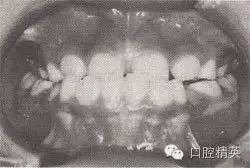

患者,女,10歲,替牙頜。磨牙近中關(guān)系。前牙反頜,下頜前突。下頜體稍長,下頜位置前移,上頜前頜骨區(qū)發(fā)育稍差。

診斷:安氏Ⅲ類前牙反猞,骨性Ⅲ類,毛氏Ⅱ¹。

矯治設(shè)計:面罩前牽引上頜,移下頜位置向后,抑制下頜生長??趦?nèi):全牙弓夾板,后牙平面頜墊式活動矯治器。矢狀關(guān)系調(diào)整后,去掉前牙區(qū)夾板,雙曲舌簧加力移切牙向唇向。

治療時間:2個月,上頜前移,下頜位置后移,切牙覆猞、覆蓋正常。

圖8-44 安氏Ⅲ類錯頜,混合牙列前牙反頜矯治前后面頜像

矯治前面相

矯治后面相